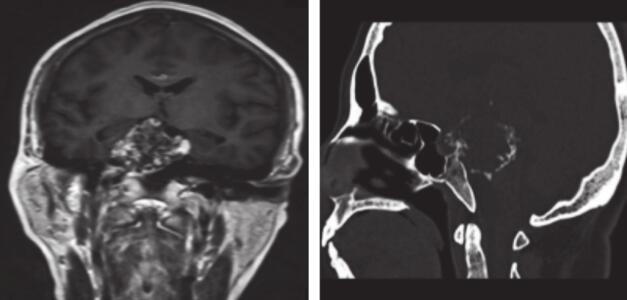

患者术后病理回报:(右中颅底)高分化软骨肉瘤。患者外科病房出院后就诊放疗中心行放疗,予6MV X线局部野IMRT放疗DT:54.75Gy/26Fx(图2),病程中予对症支持治疗。患者放疗前后(图3、图4)病灶缩小。患者随访至2017年8月,病灶稳定,症状同前。

图3 2015-3患者术后接受放疗前MRI,提示鞍上区肿瘤术后改变